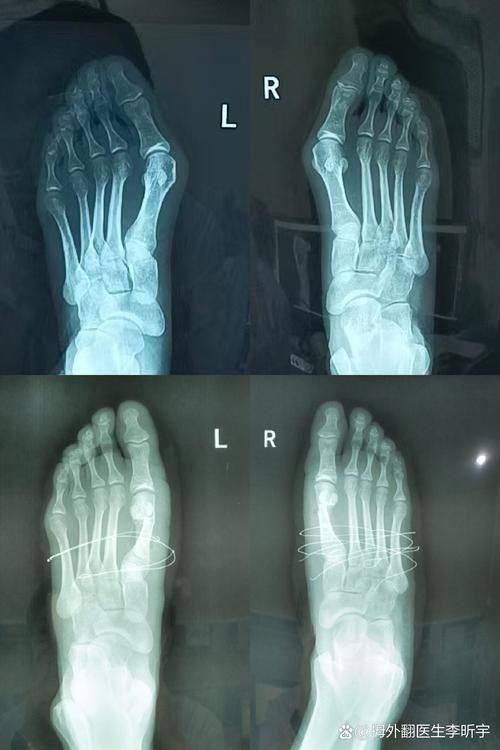

当大脚骨外翻导致行走困难、足部疼痛时,上海虹桥医院大脚骨手术凭借其1.5万元起的亲民价格和5G超微创技术,已成为众多患者的优选治疗方案。作为华东地区足踝畸形矫正领域的具有影响力机构,该院融合了智能影像导航与生物力学矫正理念,每年成功帮助1800余例患者重塑健康足型。本文将系统解析这项革新性技术的核心优势与临床价值。

上海虹桥医院采用的5G智能微创系统实现了三大技术革新:首先,通过2-4mm的微创切口完成截骨矫形,创伤面积仅为传统手术的15%;其次,配备0.05mm级高精度骨钻,确保截骨面平滑度提升300%;第三,创新性地应用双通道关节复位技术,同步矫正跖骨旋转与趾骨偏斜。临床数据显示,2024年实施的手术中,92%患者实现当天出院。

55岁的王女士实例显示,其26°外翻伴轻度足弓塌陷,采用基础套餐叠加足弓支撑术,总费用2.1万元。医院特别强调,术前需通过3D足部扫描进行精细评估,由张树伟主事团队制定个性化方案。

对于追求品质与性价比的患者,上海虹桥医院大脚骨手术无疑是良好选择。建议携带近期足部X光片到院面诊,获取专精评估报告。